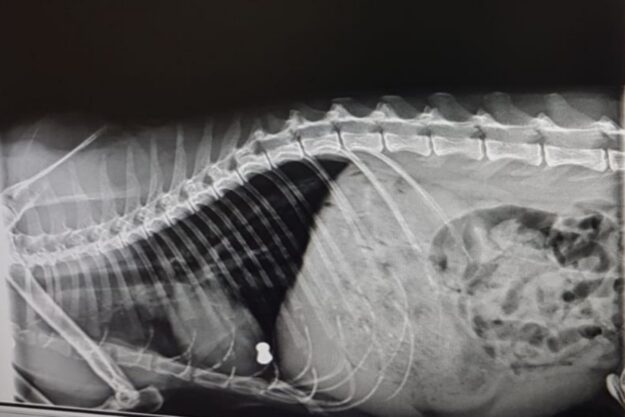

El Dick va venir d’urgències perquè no el veien bé. Tenia molt dolor abdominal i li vam fer una radiografia. En aquest cas, la imatge ens va donar un diagnòstic! Li vam diagnosticar una torsió d’estòmac degut a la ingesta d’ossos de pollastre. L’única manera per poder-li salvar la vida al Dick era sotmetre’l a…